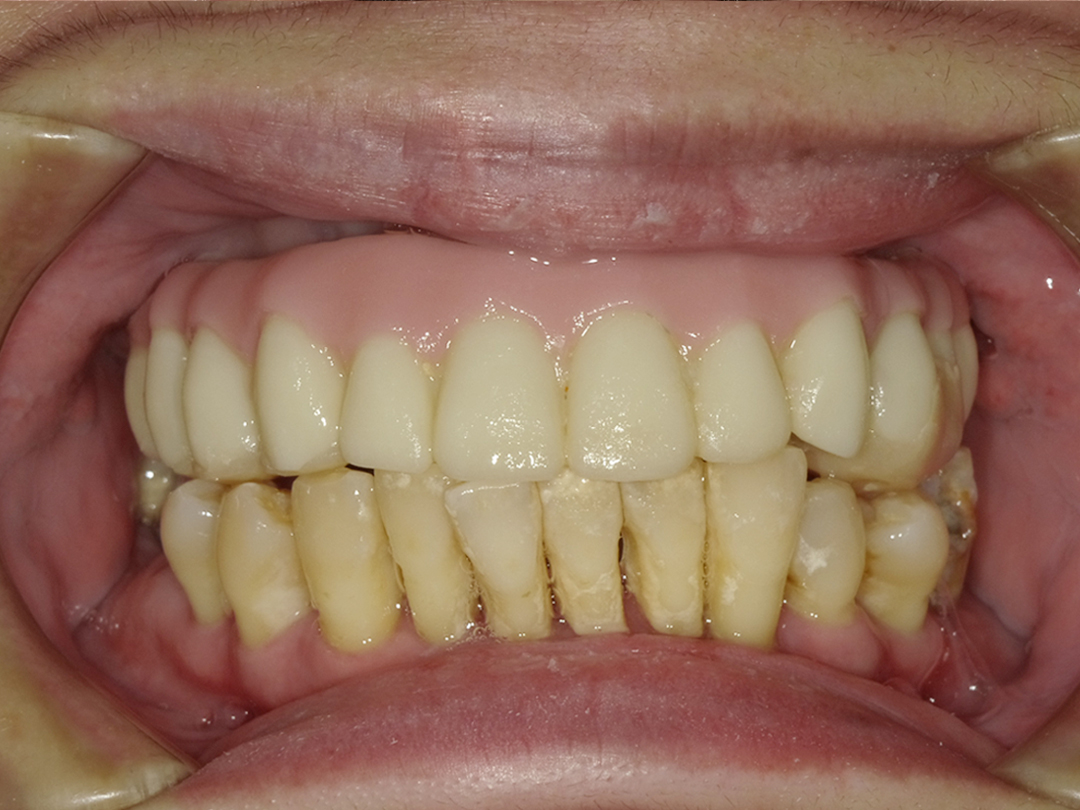

ALL ON全口重建

術式介紹

ALL ON全口重建是由4-6 顆植體(依條件而定)成,專為多顆缺牙或全口無牙患者設計的創新全口重建技術,僅需4-6 支植體即可支撐一整排固定式假牙,大幅減少手術次數與成本,並縮短療程時間。

All on 特點

適用無牙或重度牙周病患者

免補骨/少補骨即可植牙,降低手術複雜度

當天手術、當天裝牙,快速恢復日常功能

固定式牙齒,告別活動假牙的不便

美觀自然,提升生活品質與自信